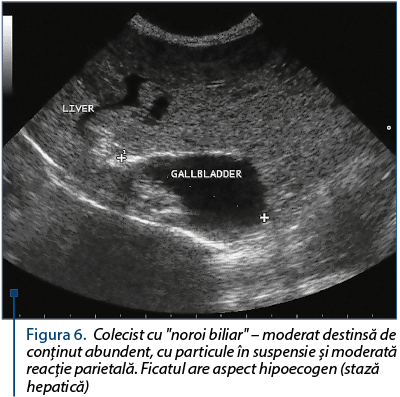

Figura 6. Colecist cu "noroi biliar" – moderat destinsă de conţinut abundent, cu particule în suspensie şi moderată reacţie parietală. Ficatul are aspect hipoecogen (stază hepatică)

Aspecte ecografice ale sludge-ului biliar: aspect ecografic stratificat, bila îşi pierde aspectul omogen transsonic (anecogen), bila capătă ecogenitate prin prezenţa elementelor corpusculare care îi dau ecogenitate proprie (figura 3 şi figura 4), dar fără umbrire posterioară. Pot apărea chiar elemente inframilimetrice (de 2-3 mm), care se pot deplasa sincron cu cinetica respiratorie sau la presiunea cu sonda ecografului (figura 5 şi figura 6).